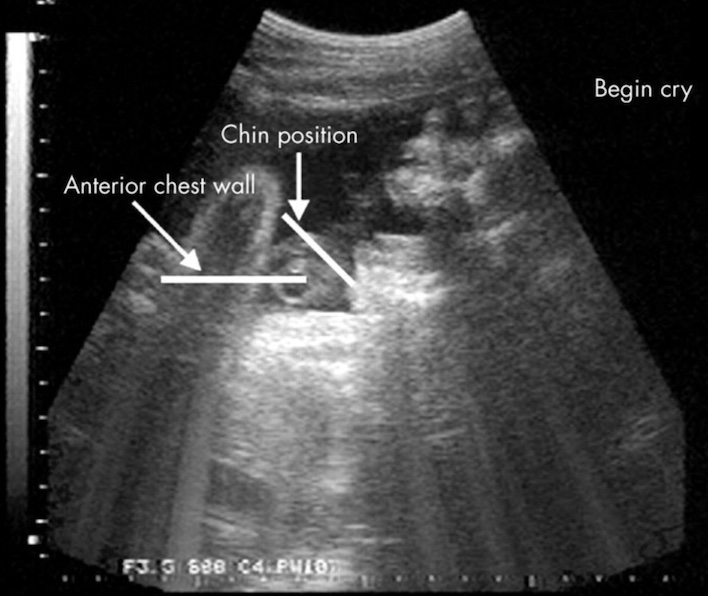

Nghiên cứu bây giờ cho thấy những đứa trẻ sơ sinh đã khóc ngay từ khi còn ở trong bụng mẹ. Mặc dù các bậc phụ huynh không cảm nhận được hành vi tinh tế này, khoảnh khắc những bào thai khóc đã được ghi nhận trên màn hình siêu âm.

Từ năm 2005, một nghiên cứu trên tạp chí Archives of Disease in Childhood – Fetal and Neonatal Edition đã báo cáo một thai nhi 33 tuần tuổi biểu hiện nét mặt như đang khóc.

Và sau khi các nhà khoa học tạo ra các kích thích rung động và tiếng ồn, thai nhi sẽ mở rộng hàm, hóp vào cằm và thở ra ba hơi lớn liên tiếp. Cùng lúc, lồng ngực đứa trẻ nhô lên và đầu ngửa ra sau. Động tác kết thúc bằng một cái rung cằm và những chuyển động này được nhìn thấy ở 10 thai nhi (khoảng 6% tổng số trẻ sơ sinh được siêu âm).